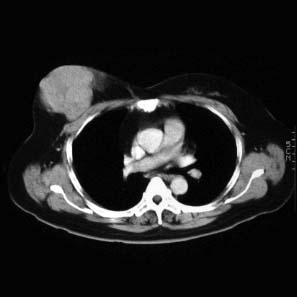

CaseKH02

- Age/Sex: 48F

- Chief Complaint: 乳房腫瘤

- Clinical Course:

- Lab. Data:

- Images:

- CT(1)

CT(2)

CT(2)

- CT(3)

CT(4)

CT(4)

- DSA1

- DSA2